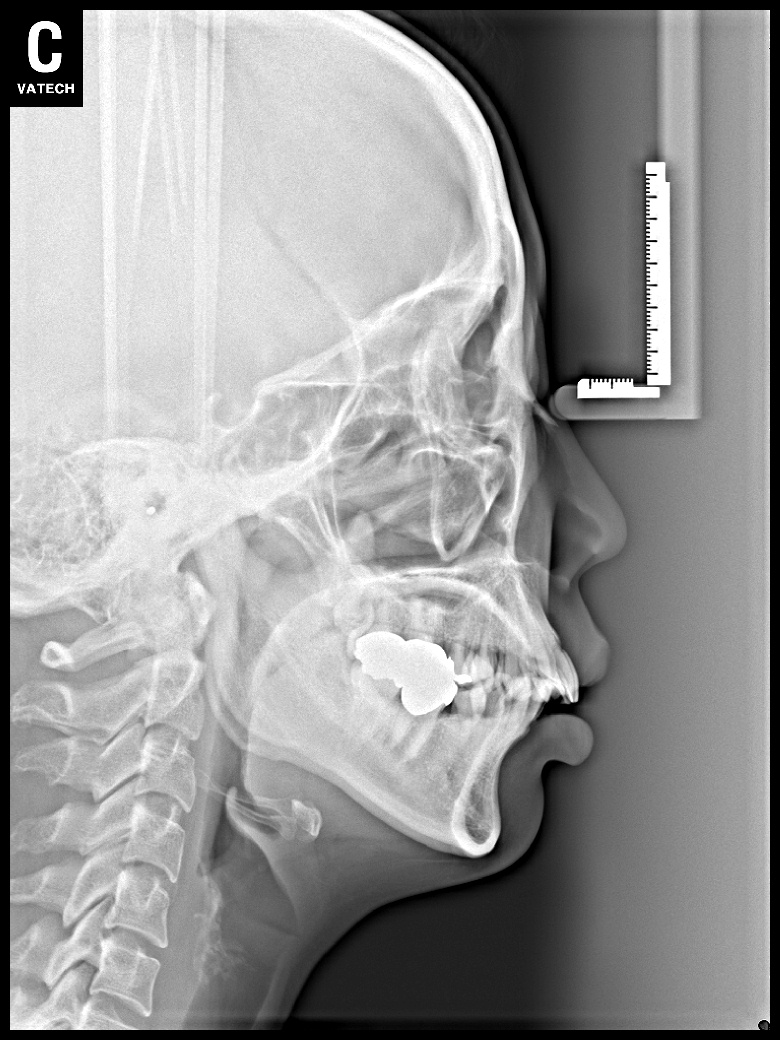

치료 전 사진입니다.